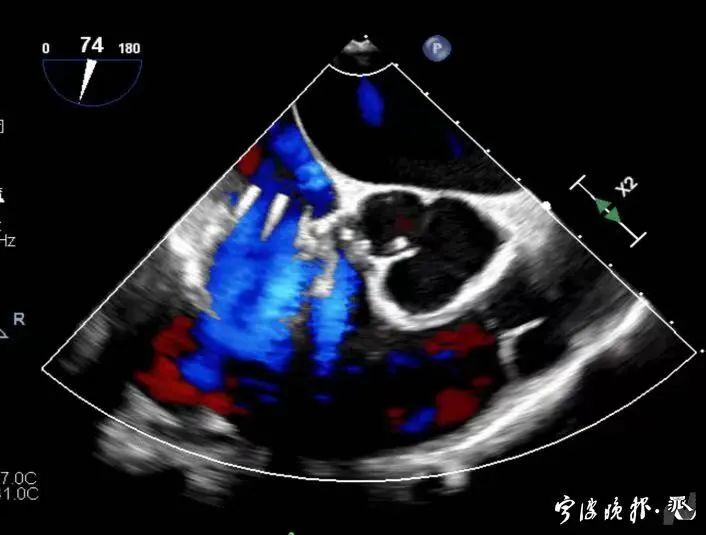

術(shù)前食道心超示三尖瓣重度反流

術(shù)后食道心超示三尖瓣反流消失

得知可以微創(chuàng)手術(shù),陳大爺一家決定放手一搏。寧波市醫(yī)療中心李惠利醫(yī)院心臟瓣膜中心團(tuán)隊(duì)反復(fù)就術(shù)前準(zhǔn)備、手術(shù)步驟及術(shù)后可能出現(xiàn)的各種情況做了預(yù)案。3月4日,陳大爺?shù)氖中g(shù)成功進(jìn)行,術(shù)中得到LuX-Valve經(jīng)導(dǎo)管三尖瓣置換術(shù)原創(chuàng)團(tuán)隊(duì),上海長(zhǎng)海醫(yī)院陸方林主任團(tuán)隊(duì)的鼎力支持,術(shù)后陳大爺?shù)男呐K三尖瓣反流立即消失。術(shù)后瓣膜中心CCU(心臟監(jiān)護(hù))團(tuán)隊(duì)和心內(nèi)科團(tuán)隊(duì)迎接一個(gè)又一個(gè)右心瓣膜置換后的血流動(dòng)力學(xué)改變等帶來的挑戰(zhàn),克服種種難關(guān),二周后患者進(jìn)入早期心臟康復(fù)。目前陳大爺已經(jīng)順利出院,沒有胸悶氣急,生活自理,精神狀態(tài)也很好,瓣膜中心團(tuán)隊(duì)也在對(duì)他持續(xù)隨訪中。